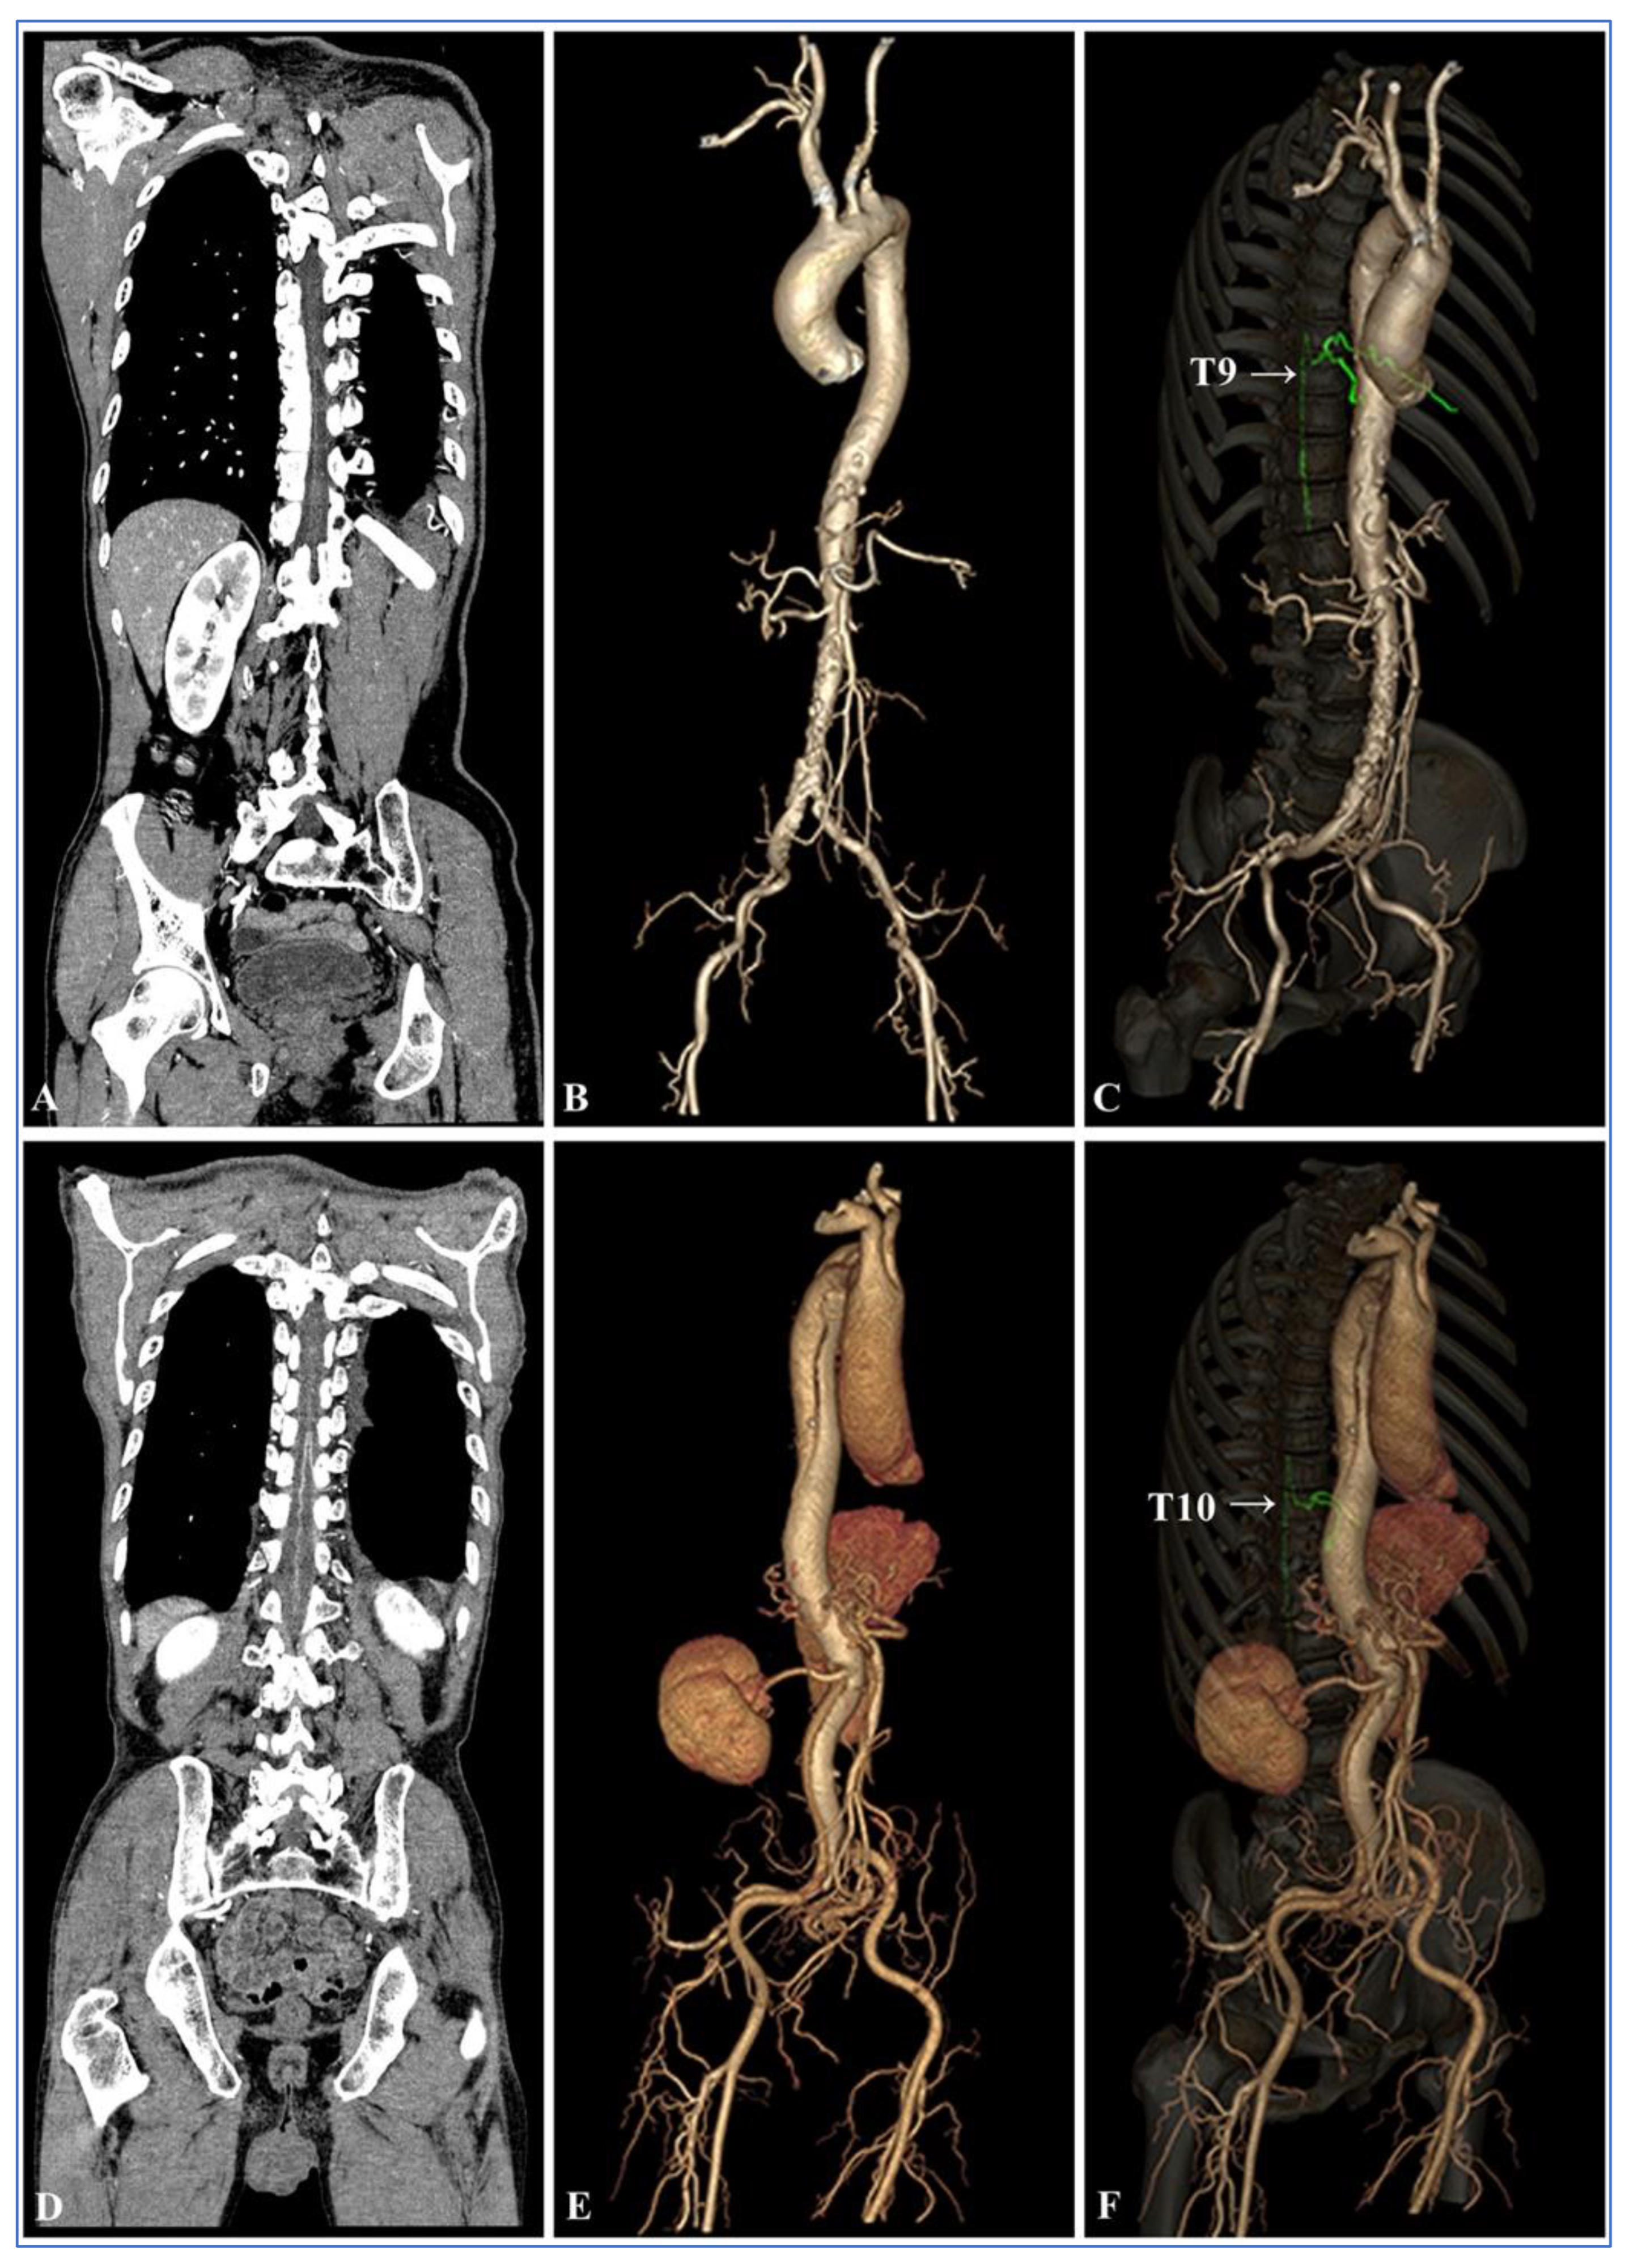

3.4. Visual Analysis of the AKA